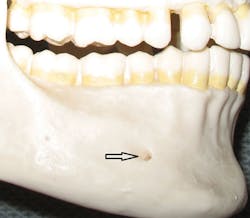

Since only the soft tissues are anesthetized by the mental block, the incisive block is preferred for nonsurgical periodontal therapy procedures. The mental foramen, which opens anteriorly and superiorly, is usually located near the apex of the second premolar (see Figure 2), although studies indicate that it can be located from the distal of the canine to the first molar.3-5 It is advisable to check the radiographs and palpate the area prior to procedures to determine its location. The foramen appears as a round or oval radiolucency on radiographs (see Figures 3, 4) and may be palpable as a concavity or rough elevation.2

Figure 2: Mental foramen